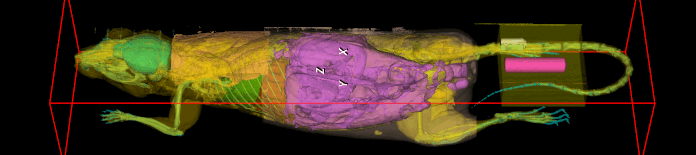

PET/SPECT/CT (3D X-Ray and nuclear imaging)

Mediso NanoScan PET/SPECT/CT

- 3D Soft Tissue and Bone Imaging

o Lung Scans

o Full Body Reconstructions - Nuclear Imaging (Tc99M and 18F compounds)

o 18FDG – glucose uptake

o Tc99M – Sodium/Iodide Cotransporter expression localization

o Inquire about other application - Core workstations include access to VivoQuant software for reconstructions, segmentation, and analysis